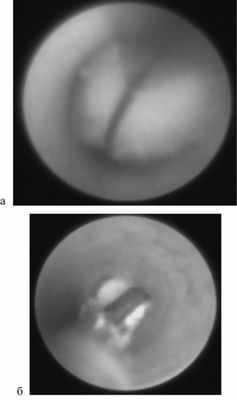

Рис. 1. Удаление конкремента. а — протоковыми щипцами; б — «корзиной».

Данная методика по сути явилась наиболее щадящей и миниинвазивной, но, к сожалению, такие идеальные условия для ее применения в наших наблюдениях встретились лишь у 92 из 317 пациентов. При этом в 14 случаях конкременты располагались в околоушной слюнной железе, а в 78 — в подчелюстной.

2. При наличии более крупных конкрементов, выведение которых через устье протока не представляется возможным, использовалась вторая методика, основанная на дроблении данных камней при помощи внутрипротоковой контактной лазерной литотрипсии с последующей экстракцией осколков «корзиной» (рис. 2). По данной методике нами прооперировано 52 пациента. На первых этапах внедрения сиалоэндоскопии в повседневную практику использование контактной лазерной литотрипсии казалось нам методом выбора, но, к сожалению, применение данной методики с помощью имеющегося в нашем распоряжении эндоскопического гольмиевого лазера модели Auriga XL оказалось возможным лишь в случае нахождения камня непосредственно в зоне прямой видимости, а так же при условии его неподвижности в протоке. При несоблюдении данных условий, по нашему предположению, вероятна интраоперационная термическая травма эндотелия протока или даже сквозная перфорация его стенки с миграцией конкремента в окружающие проток ткани железы.

Рис. 2. Лазерная литотрипсия. а — момент процедуры эндоскопического дробления конкремента; б — этап последующего удаления фрагментов разрушенного конкремента протоковыми щипцами.